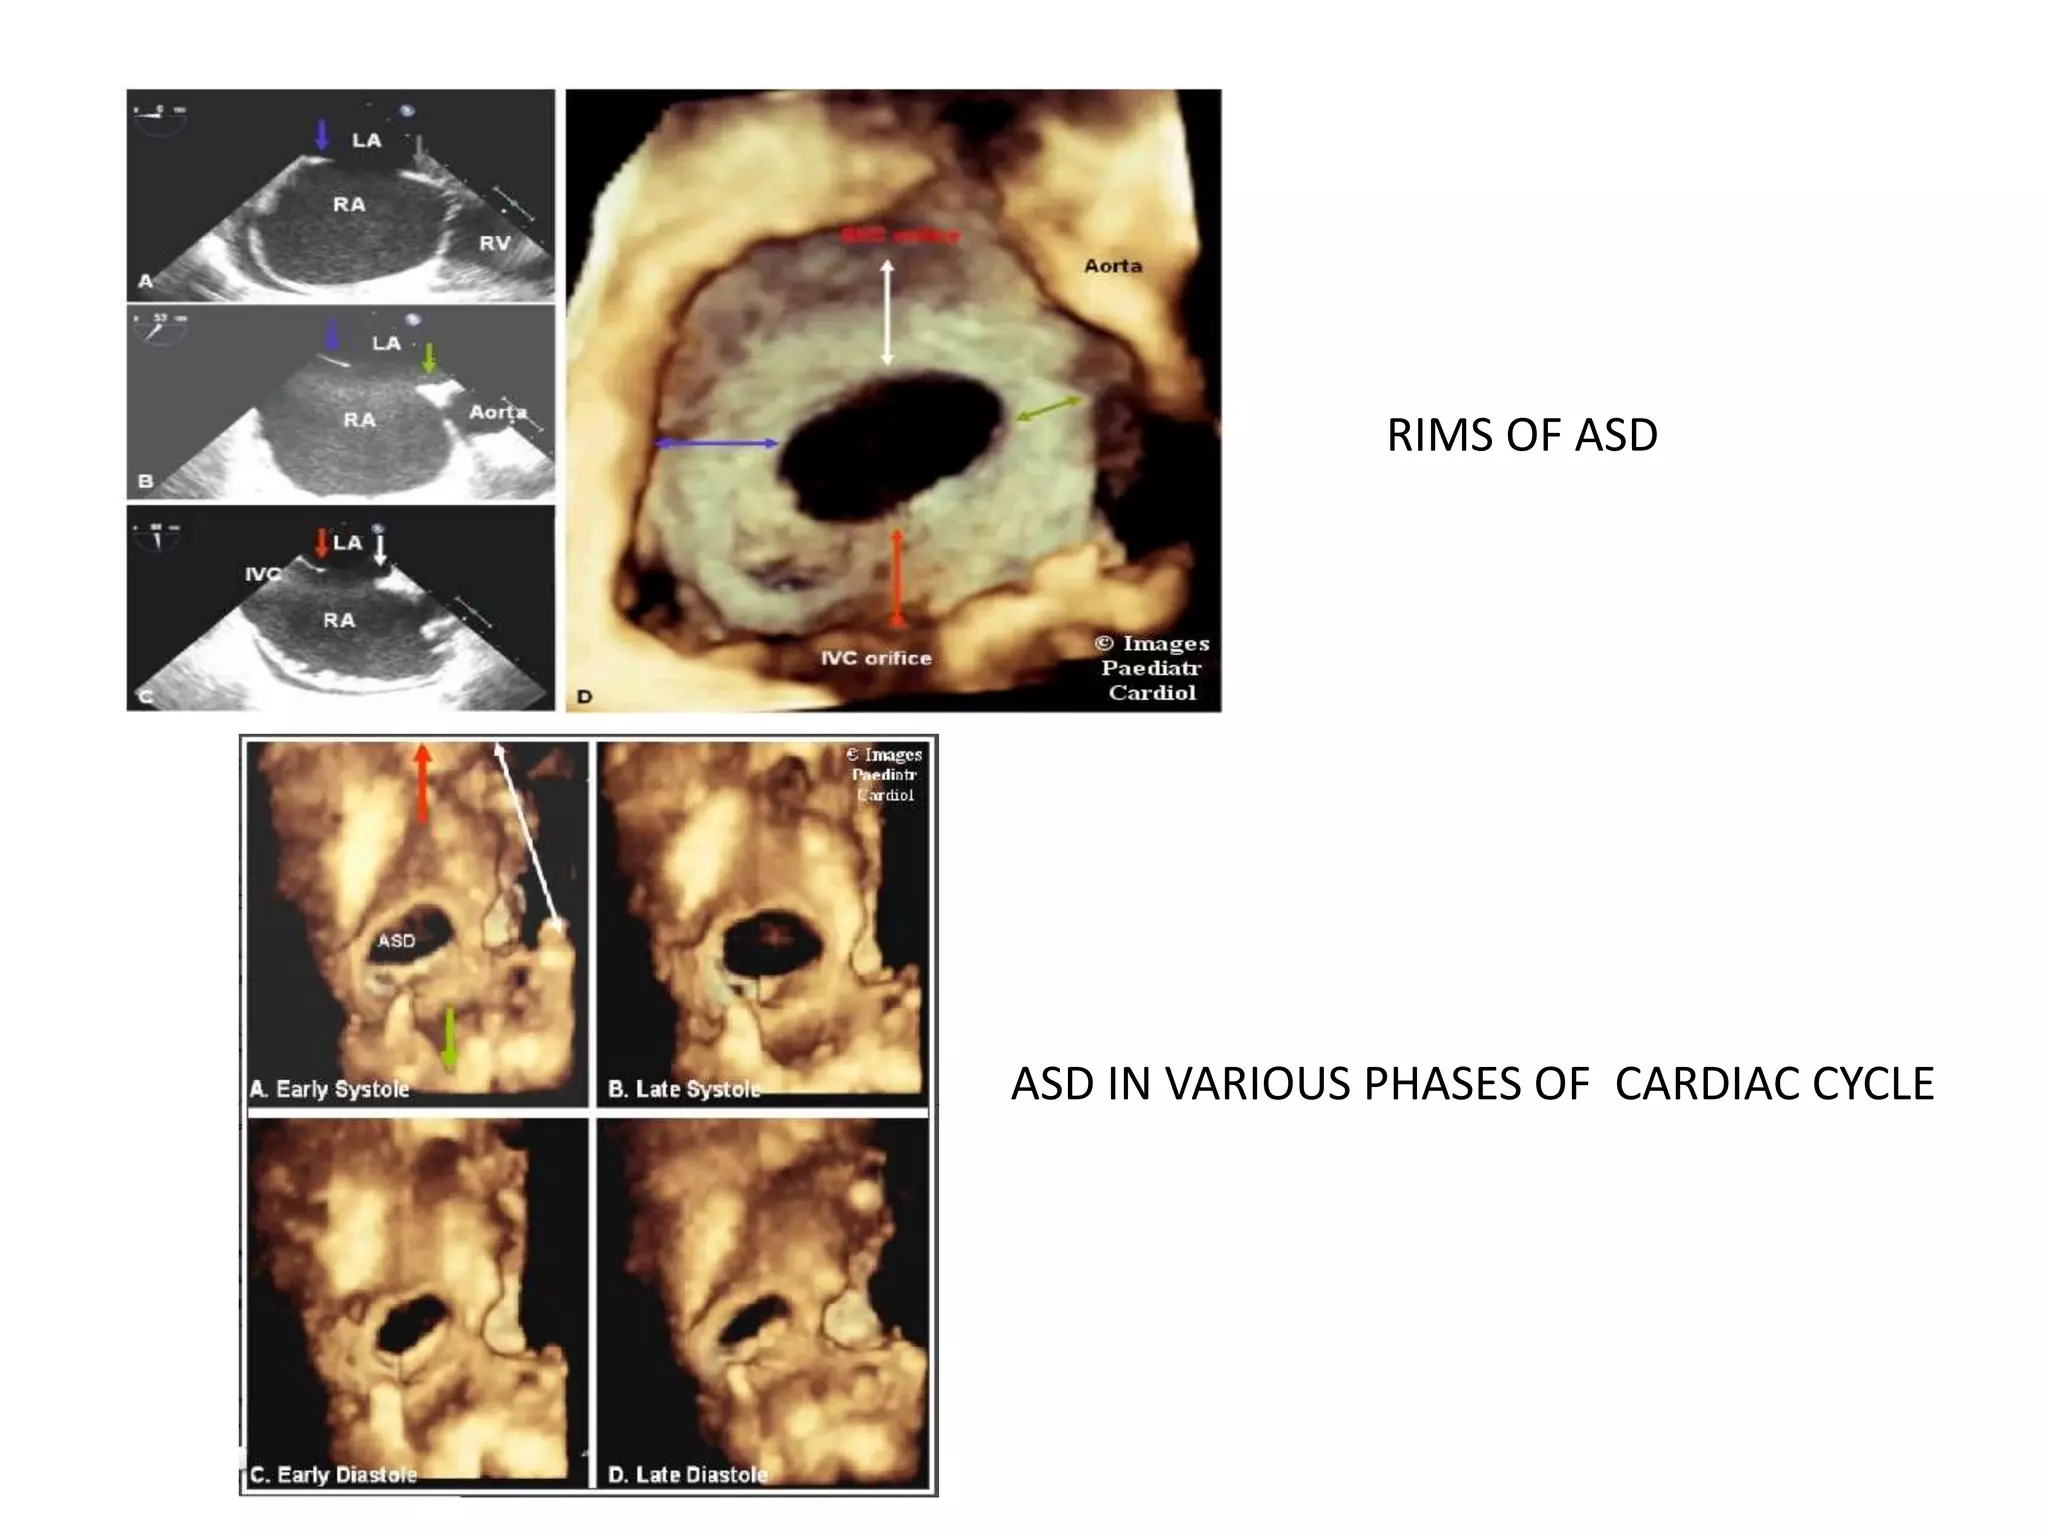

RIMS OF ASD

Aortic - Superoanterior

Atrioventricular (AV) valve -mitral or inferoanterior

Superior Vena Caval SVC – Superoposterior

Inferior venacaval (IVC or Inferoposterior) Posterior

(from the posterior free wall of the atria).

IVC AND SVC RIMS

OTHER RIMS

Measurement of the ASD rims

• Atleast 5 mm

• IVC rim-most important

Schematic representation of the

locations of the ASD rims

• Real-time 3D imaging demonstrates the

changing shape of the ASD during a cardiac

cycle, with maximum size in diastole

ASD IN VARIOUS PHASES OF CARDIAC CYCLE

RIMS OF ASD Aortic- Superoanterior Atrioventricular (AV) valve -mitral or inferoanterior Superior Vena Caval SVC – Superoposterior Inferior venacaval (IVC or Inferoposterior) Posterior (from the posterior free wall of the atria).

Measurement of theASD rims • Atleast 5 mm • IVC rim-most important Schematic representation of the locations of the ASD rims

RIMS OF ASD ASDIN VARIOUS PHASES OF CARDIAC CYCLE